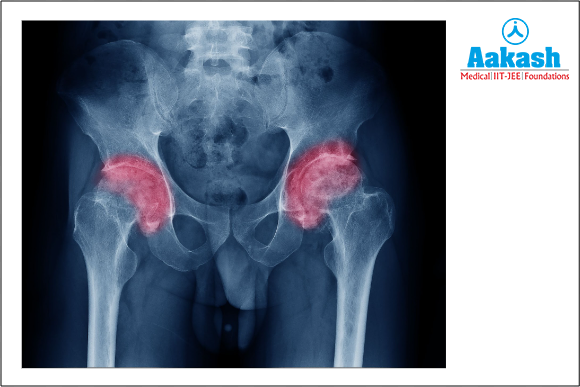

Hip osteoarthritis is another prevalent condition that can affect one or both hips. The hip joint is a type of ball-and-socket joint that normally possesses a wide range of movement. The hip bears a lot of body weight. Osteoarthritis in the hip joint is common in men as well as women.

Fig: Osteoarthritis in the hip joint